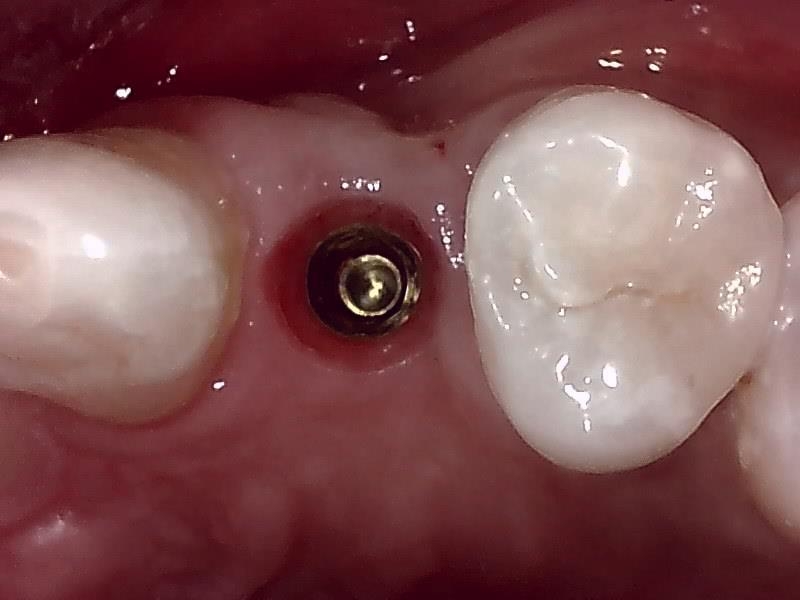

抜糸後

歯肉の整形

術中インプラント埋入したあと、アバットメントの装着のため

歯肉の整形 (左上)とても綺麗な良い歯肉の状態です。